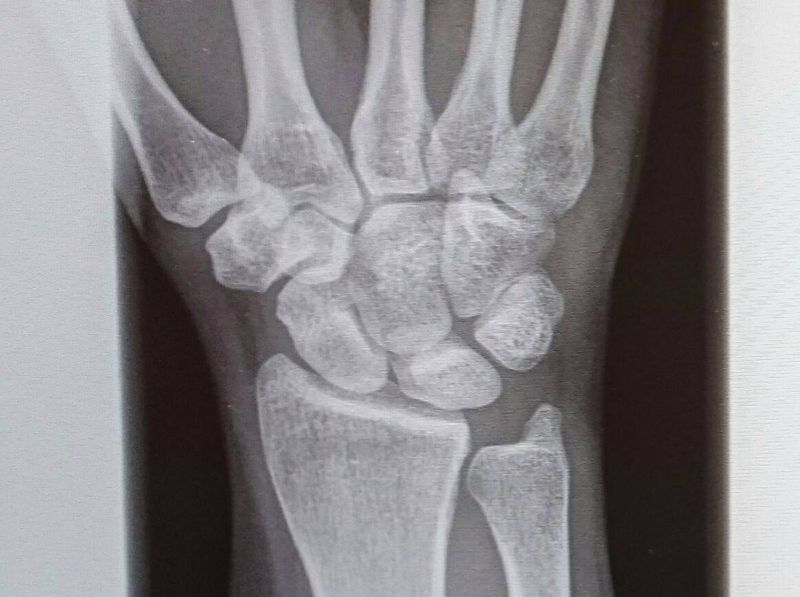

![Abb. 2 8 Radiusköpfchenfraktur Typ III nach Mason. (Aus [6]) Download Scientific Diagram Abb. 2 8 Radiusköpfchenfraktur Typ III nach Mason. (Aus [6]) Download Scientific Diagram](https://www.researchgate.net/profile/Hanjo_Neumann/publication/267154228/figure/fig1/AS:392161469190154@1470509988898/Abb-2-8-Radiuskoepfchenfraktur-Typ-III-nach-Mason-Aus-6.png)

Abb. 2 8 Radiusköpfchenfraktur Typ III nach Mason. (Aus [6]) Download Scientific Diagram